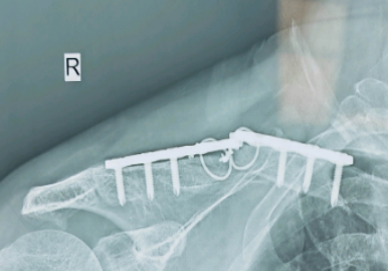

然而,少数患者(约1%-3%)在术后可能出现钢板断裂的情况,这不仅影响康复,还可能需要进行二次手术(如下图所示)。

双钢板技术(适用于严重骨质疏松患者)如下图。

-